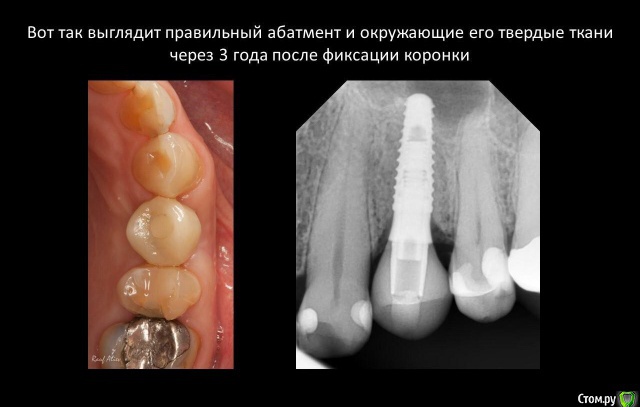

Я вот, в общем то, о том же. Но почему за 4 года в этом случае все стало только лучше? Что-то в моей философии о БШ, значит, неверно

У Вас получилось «не благодаря ,а вопреки». На каком то этапе наросла кость на плечо импланта и все живет . Обычно получается как r_b показал(кошмар! Такую работу запороли). В общем,на авось прокатит надеяться не надо,лучше не давать повода и контролировать каждый этап. И беречь десну,будет прикреплённая десна-будет и кость-будет жив имплант.

Я долгое время считал разделение платформ и/или соблюдение БШ ключевыми факторами для стабильности периимплантных тканей (при адекватной нагрузке по умолчанию). А это, видимо, не так.